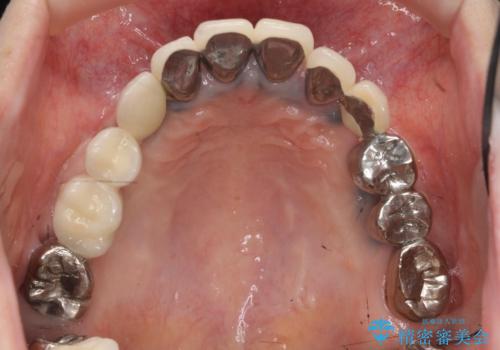

全顎的 虫歯治療 インプラント補綴

- 「他院で虫歯治療を行っているが、延々終わらず数年経過している。全体的な治療を希望したい。」と全顎的な治療を希望され来院されました。

・再発した虫歯

・銀歯の下にできた虫歯

・根尖性歯周炎

・残根状態の歯

など、虫歯を原因とする問題が多発した状態です。

今後延々と治療を繰り返さないために、全ての銀歯を外し虫歯を丁寧に取り切り、根管治療を行い、残せない歯は抜去を行った上でインプラント治療を行っていくことで全体的な治療を計画していくこととなりました。